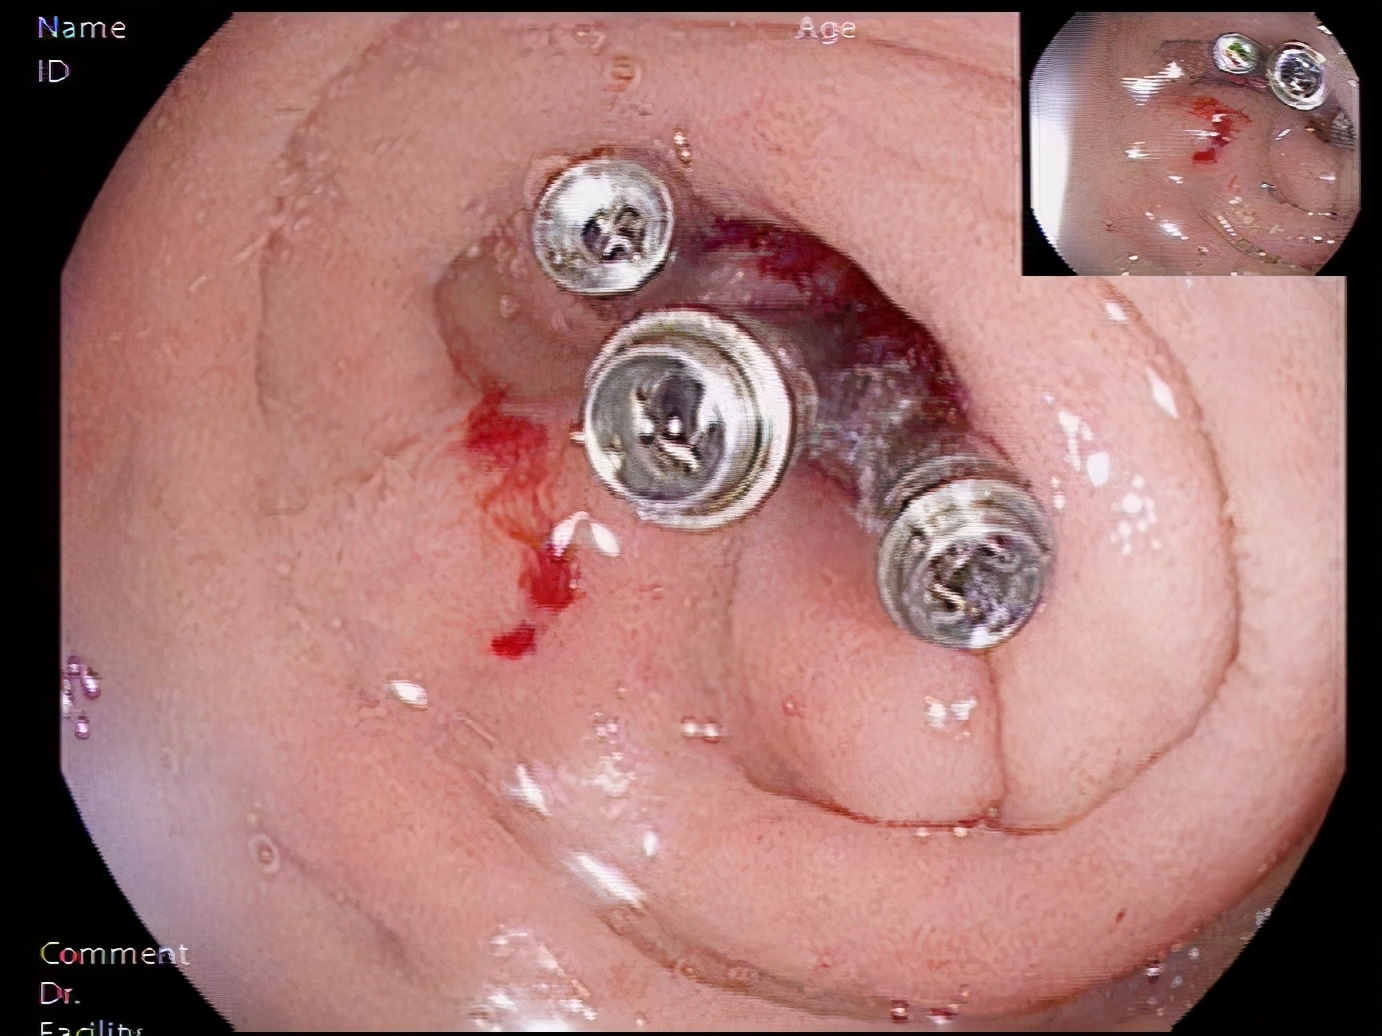

经过麻醉评估,15:40赵世民副主任医师开始内镜检查,发现患者十二指肠球降移行部有一处病灶,有活动性渗血,林涛主任指示行钛夹封闭创面治疗,于16:00顺利完成内镜下钛夹止血术。患者入院不到六小时就完成内镜下止血治疗,比急性上消化道出血救治快速通道国家标准的12小时缩短了6小时,体现了大兴速度。千方百计对患者好,用最短的抢救时间,最优质的医疗技术,给患者最优质的健康保障。

用钛夹夹闭病灶